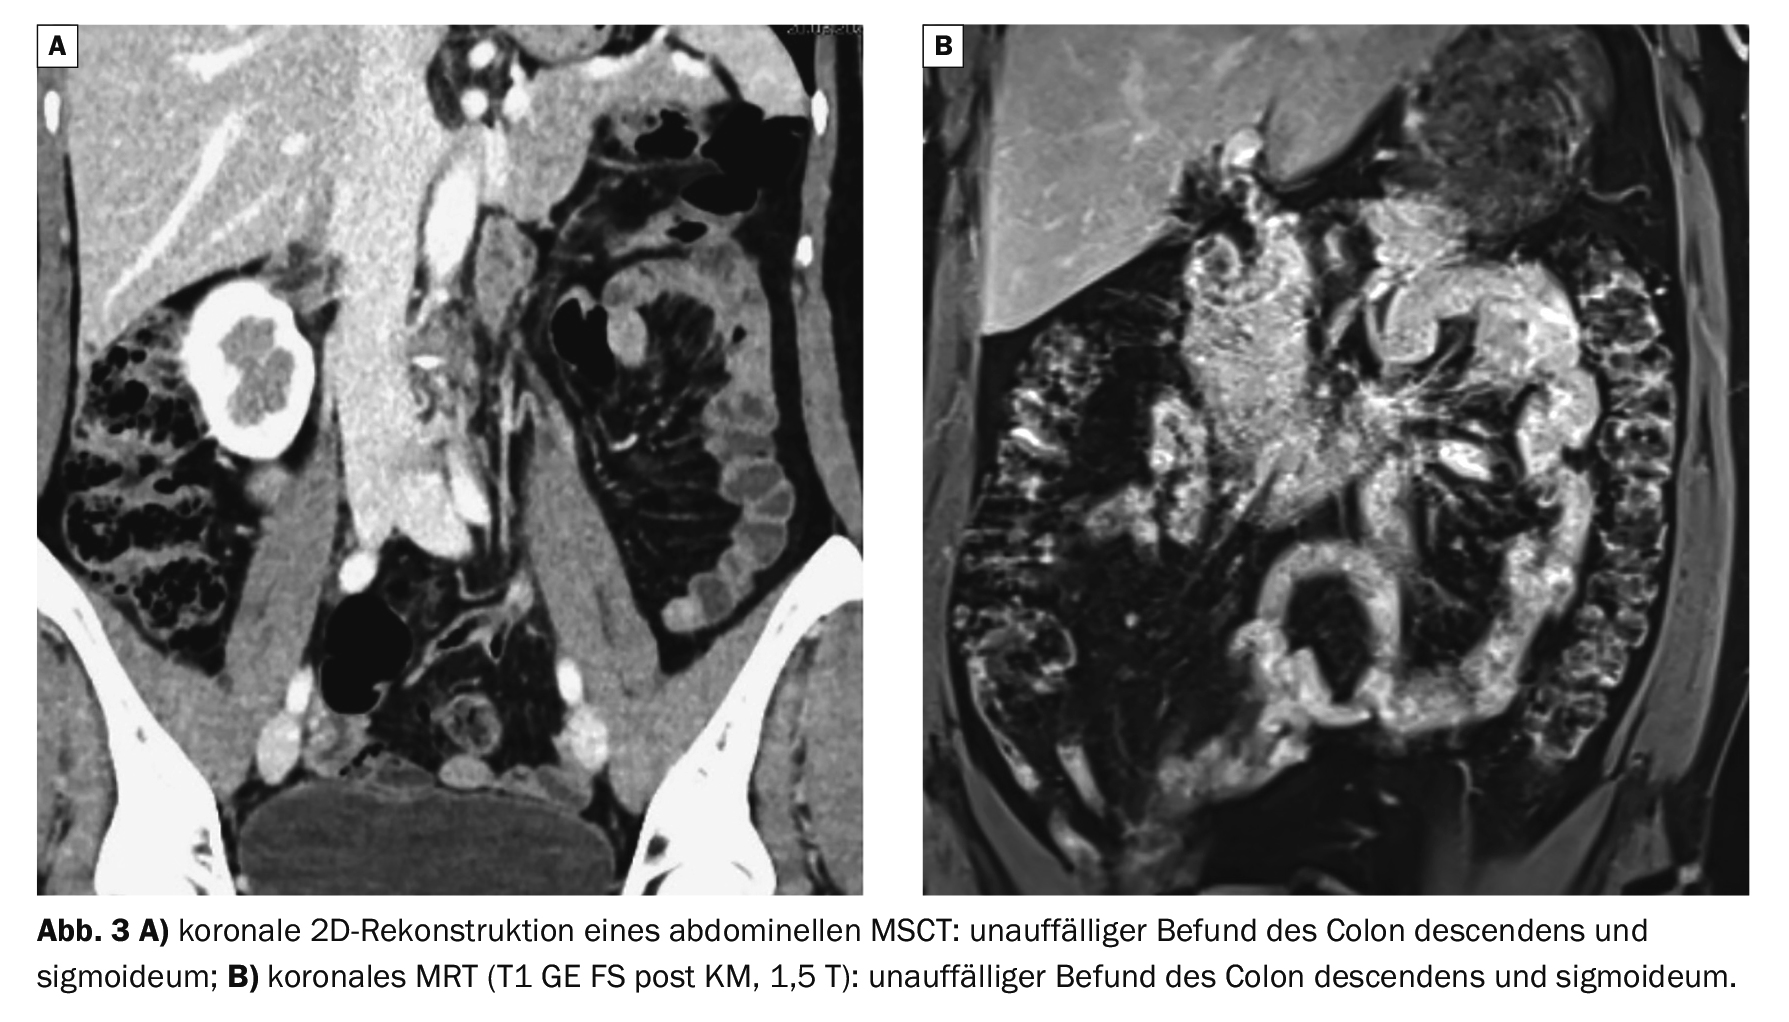

Dans l’exemple 3 , les résultats normaux du côlon sigmoïde au scanner (Fig. 3A) et à l’IRM (Fig. 3B) sont présentés à titre de comparaison.